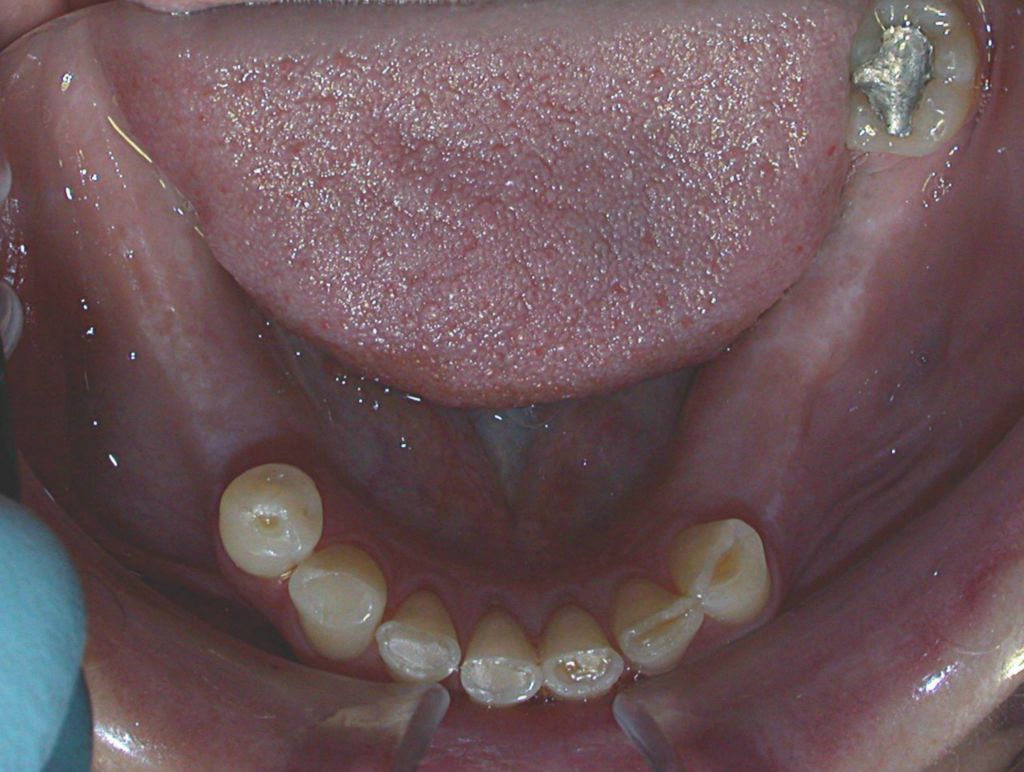

Before

After